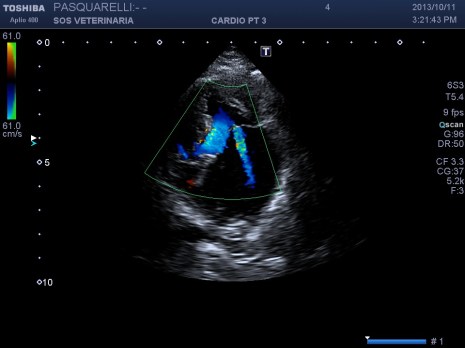

Per avere una idea del grado di pericolosita’ della malattia basta visionare lo smoke (effetto fumo) nell’atrio sx del soggetto e il voluminoso trombo fluttuante e martellante i lembi valvolari .